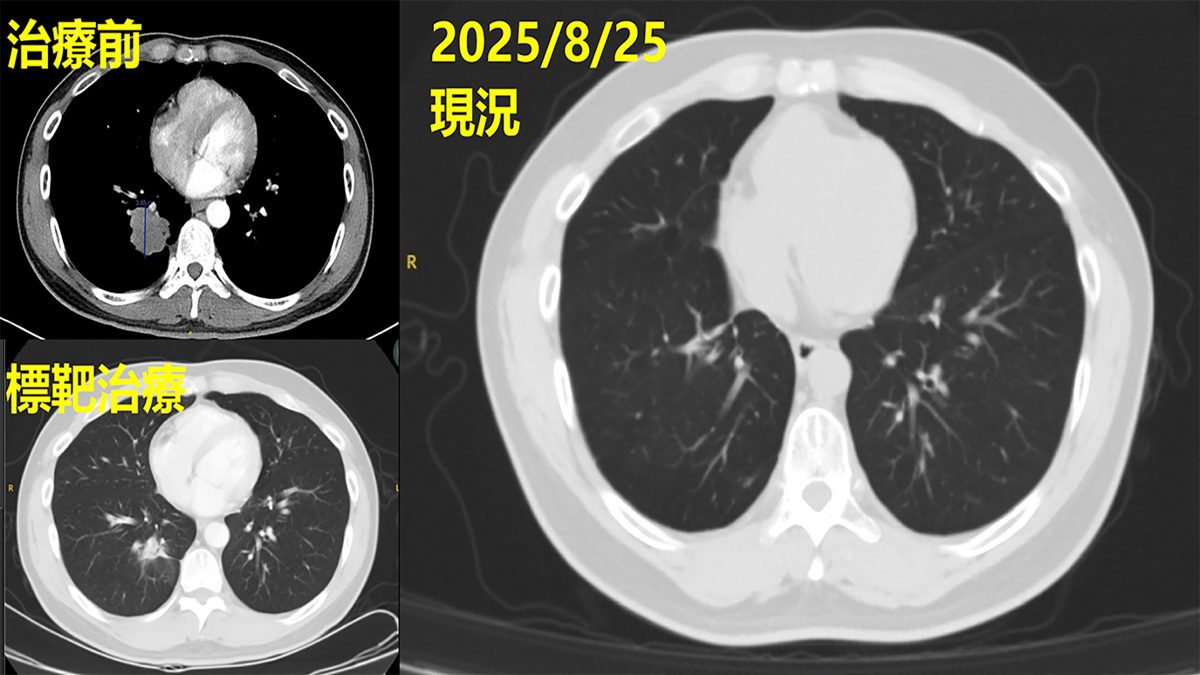

「病人剛入院時,我們先依臨床流程完成初步的基因檢測,但結果未發現可使用的突變標靶。」林聖皓主任說明,後續團隊持續評估治療方向,並協助病人參與國家衛生研究院的臨床基因試驗,最終發現具EGFR exon 19 deletion突變,得以申請第三代EGFR標靶藥物,使治療更具針對性與精準性。經過一段時間,影像追蹤顯示肺部腫瘤從原本的4公分縮小為2.8公分,控制成效顯著。

▲經治療後影像追蹤可見,原近4公分腫瘤明顯消失,病情獲得良好控制。(圖/彰基提供)